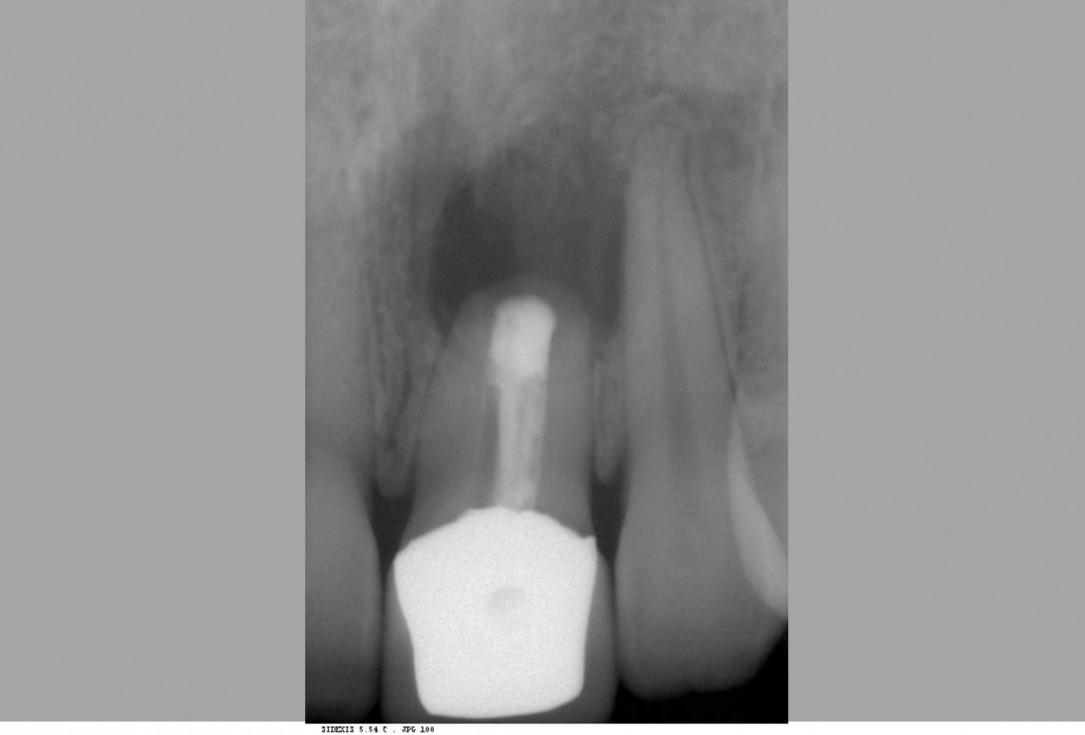

02/12 - Extraction of tooth 21 after endodontic treatmentTreatment of dehiscence defect with cerabone® & Jason® membrane - Dr. M. Steigmann